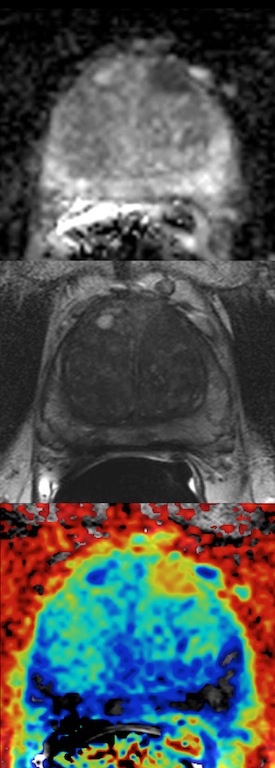

- Prostate Cancer

Prostate Cancer

The program in prostate cancer research is a multidisciplinary effort that includes the Departments of Radiology, Pathology, Urology, and Radiation Oncology, as well as the Harold C. Simmons Comprehensive Cancer Center.

The mission of this program is to promote innovative, high-impact, translational research that improves clinical outcomes through better tools to detect clinically relevant disease and distinction of aggressive versus indolent forms of the disease.

Current projects involve the role of imaging-pathology reconciliation, the optimal biopsy strategy in men with abnormal multiparametric MRI, refining structured MRI reporting for detection and staging, and the validation of quantitative markers of disease aggressiveness.